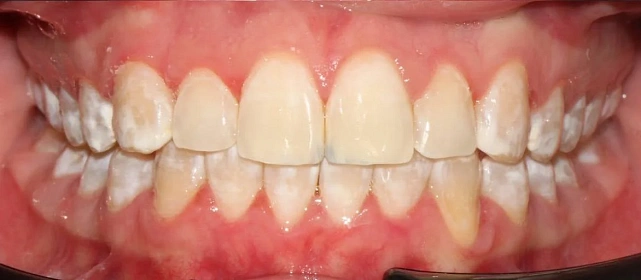

Проблема: Пациентку не устраивало положение зубов и то, как смыкаются челюсти. Зубы стояли неровно, ряды сходились неправильно.

Нарушение соотношения челюстей и неправильное положение зубов — зубные ряды смыкались некорректно, зубы стояли со смещением.